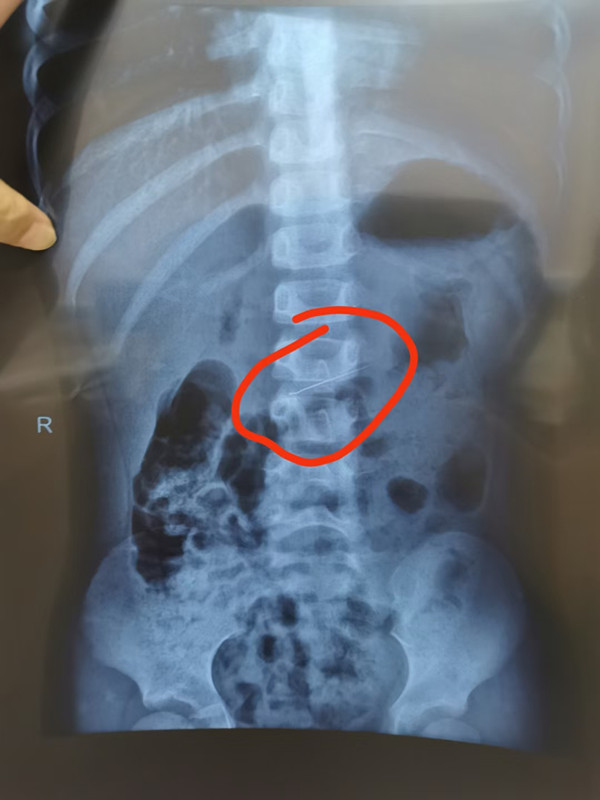

针在胃,立即手术图片

耳鼻喉科医生马上联系内镜中心,副主任边鹏火速赶来。经检查,针真的在悠悠胃里。情况紧急,为避免针划伤胃壁、损伤肠道,需要立即手术取针。内镜中心医生立刻给悠悠做了术前采血,一系列准备完毕后,悠悠全麻进入手术室。